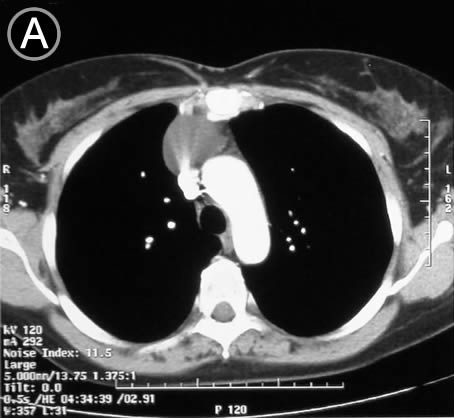

Corte Tomográfico A

Sección transversal a la altura del cayado aortico

Lesión homogénea redondeada, bien limitada, anterior al cayado aortico, hacia hemitorax derecho.

El resto de la imagen de aspecto normal.